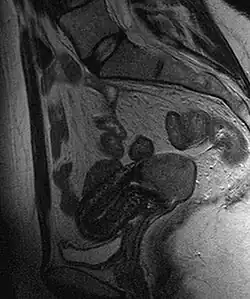

Câncer do colo do útero visto em imagem de ressonância magnética da pelve em T2, posição sagital.

Este grande carcinoma escamoso (na parte inferior da imagem) obliterou o colo e invadiu o segmento inferior do útero. O útero também apresenta um leiomioma arredondado em sua parte superior.

Frequentemente, antes da biópsia, o médico solicita exames de imagem para descartar outras causas para os sintomas da paciente. Algumas modalidades de imagem incluem a ultrassonografia, a tomografia computadorizada e a ressonância nuclear magnética, que têm sido usadas na busca por outras doenças, para identificar extensão do tumor e seu efeito sobre estruturas adjacentes. Tipicamente, o tumor se apresenta como uma massa heterogênea no colo.[35]